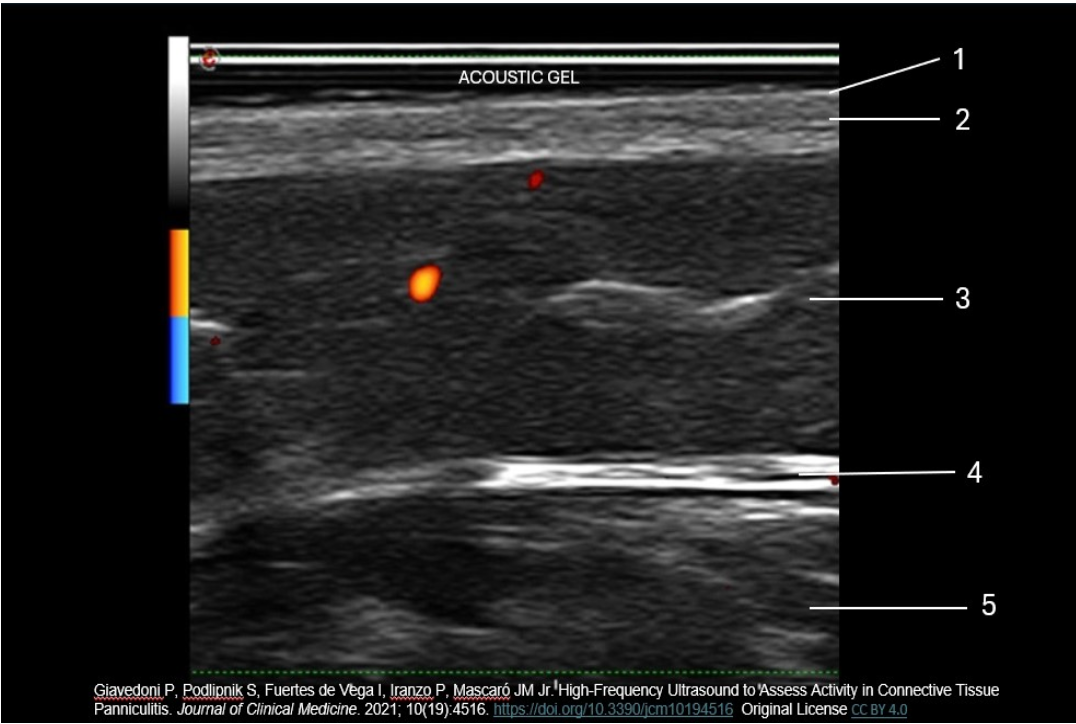

Which number indicates the dermis layer of the skin?

B. 2